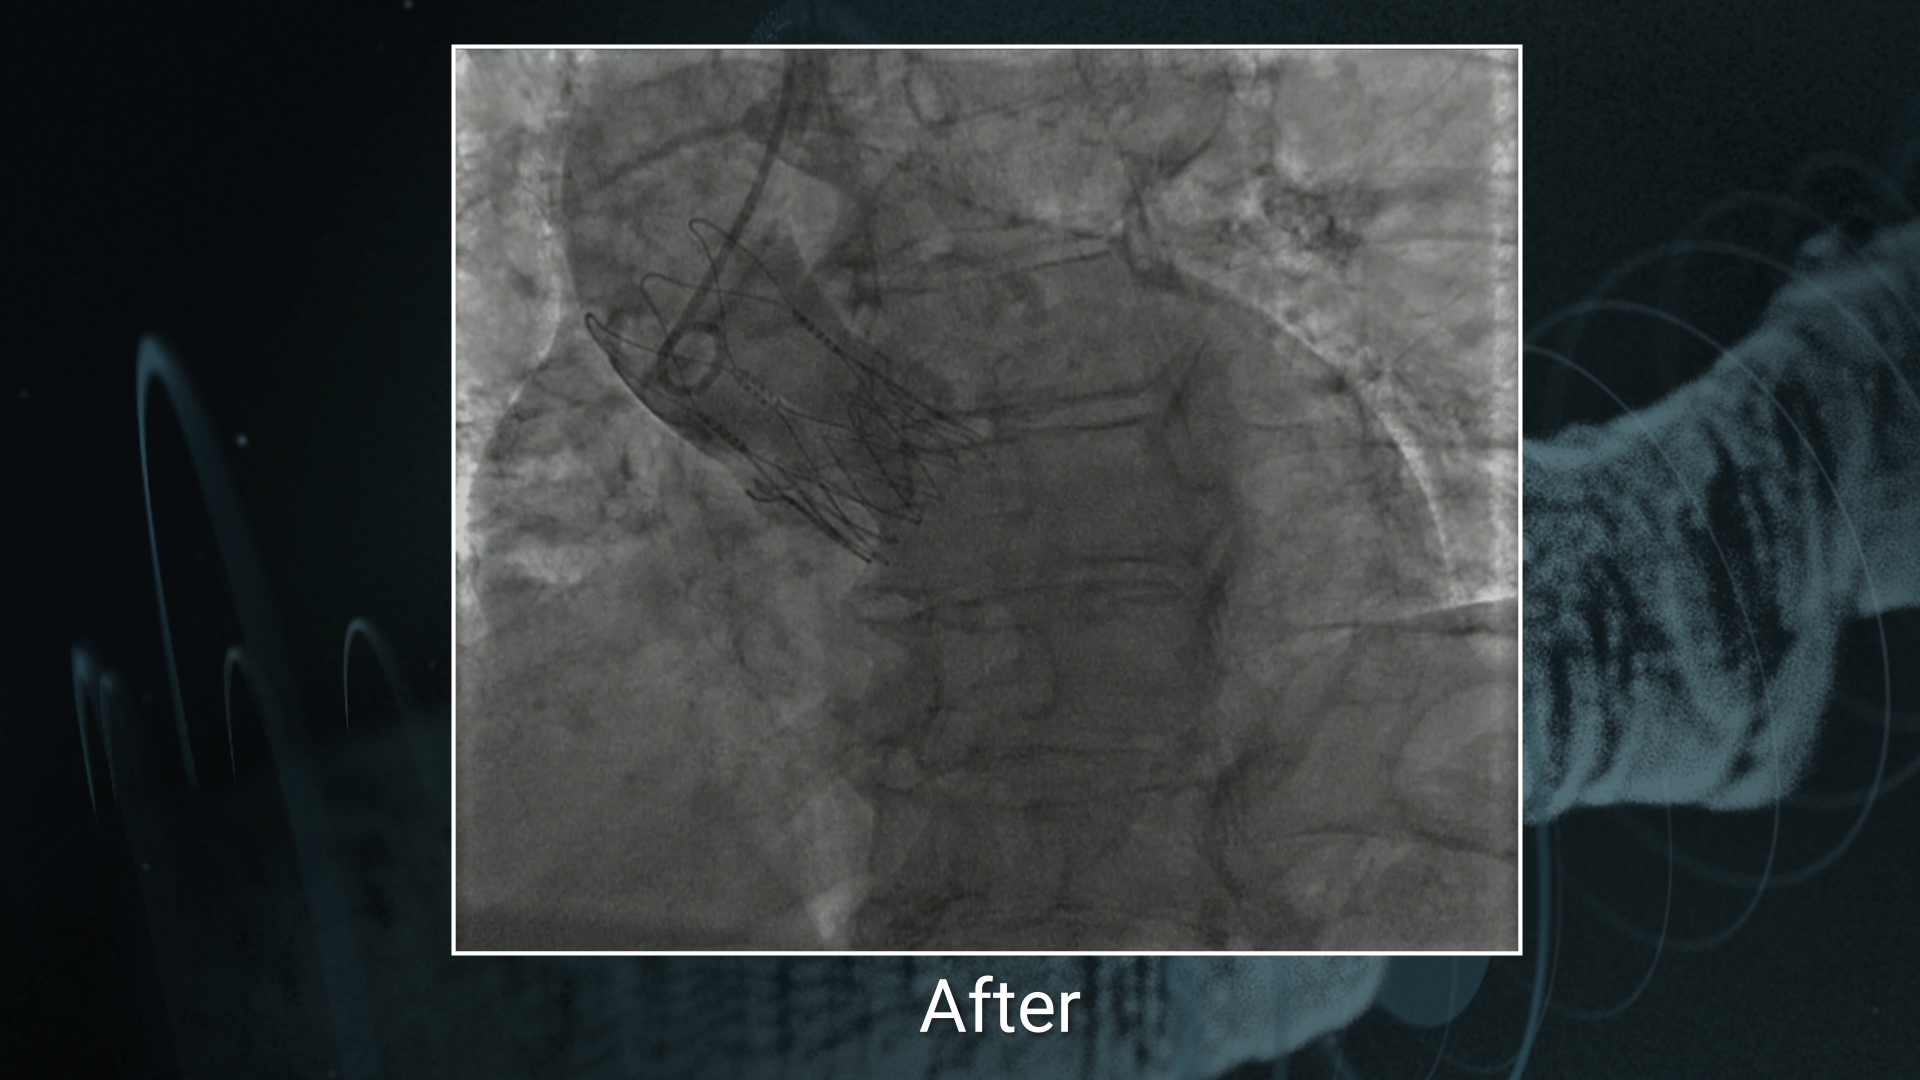

• venkatesa reddy D. very well demonstrated how to treat double bifurcation in simple method

MEGATRON in Ostial & LM lesions / ACURATE neo in TAVI